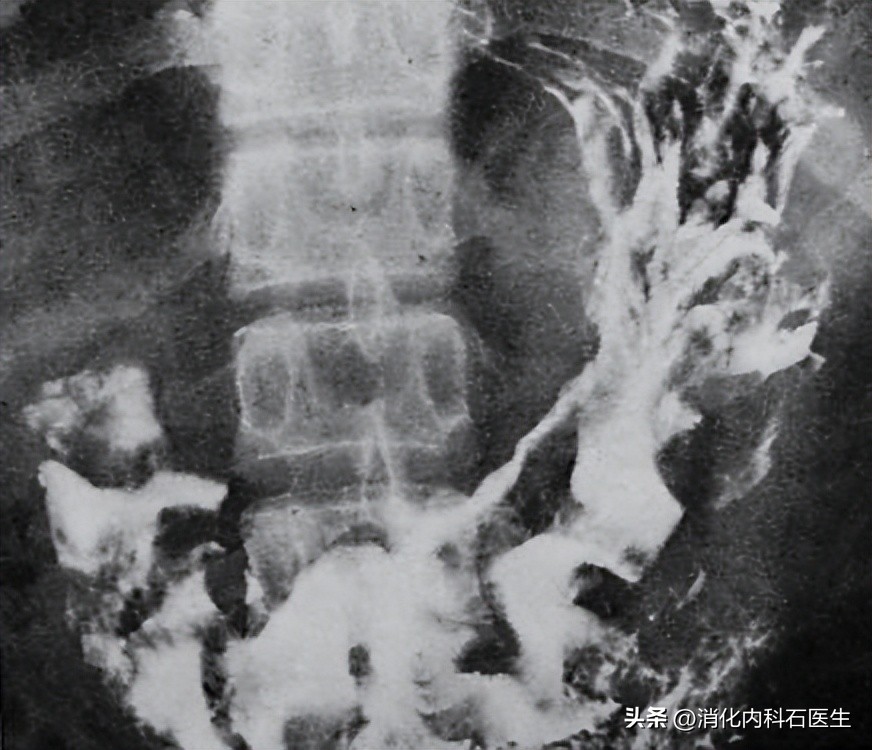

钡餐透视,真的发现了问题:

胃内有一个巨大的胃石。

上腹部钡餐透视